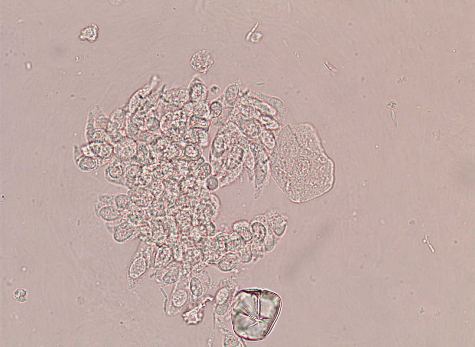

円柱上皮細胞  カテーテル尿

大きさは15〜40μmで立方体から円柱状を示す カテーテル尿の場合柵状配列を呈することがある。

線毛を有したり、脂肪化しているものもある。深層の移行上皮細胞との鑑別が必要